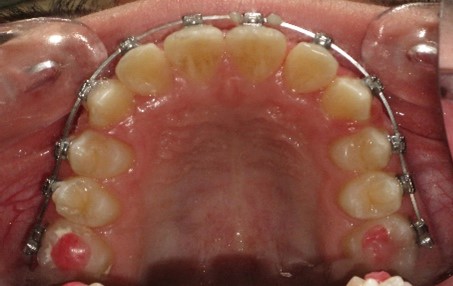

После дистализации боковых сегментов на верхней челюсти и правильной постановки клыков в зубной ряд проведена фиксация аппарата на нижний зубной ряд и дальнейшая коррекция окклюзии проводится по стандартному протоколу, т.е. нормализация формы зубных рядов на верхней и нижней челюсти с правильной постановкой зубов по торку в боковых и во фронтальном отделах, что дает реализация программы, заложенная в пассивной самолигирующей брекет- системе NexStep Pro 0.22. (рис.8)

Рис.8. Этап контроля торка на верхней челюсти и фиксация аппарата на нижней челюсти для проведения этапа нивелирования.